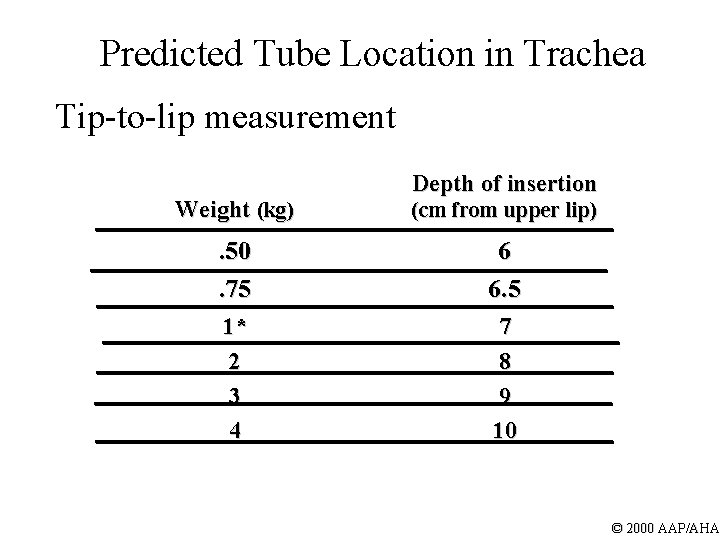

Predicted Tube Location in Trachea Tip-to-lip measurement Depth of insertion Weight (kg) (cm from upper lip) . 50. 75 6 6. 5 1* 2 3 4 7 8 9 10 © 2000 AAP/AHA